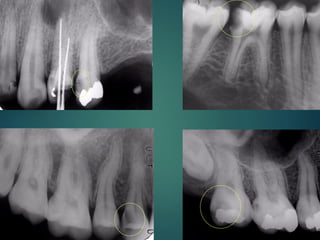

Clasificación Radiográfica

De Las Caries

Incipiente de esmalte

De esmalte

Dentinaria superficial

Dentinaria profunda

Sobreproyectada en cámara pulpar

Penetrante

 Incipiente de esmalte

 De esmalte

 Dentinaria superficial

 Dentinaria profunda

 Sobreproyectada en cámara

pulpar

 Penetrante

Diagnostico Radiografico de Caries